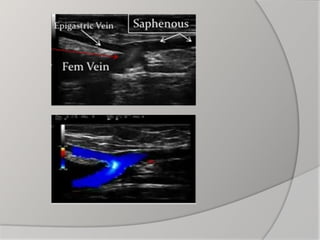

- Duplex ultrasound: The best; gives both anatomical

and functional diagnosis

- Others: e.g. CT venography and MRI rarely needed

 Duplex US is essential to identify

superficial, deep or perforator vein reflux

 General: - Assessthe general condition of the patient: e.g. CBC,liver and kidney function tests  Specific: - Hand-held Doppler - Duplex ultrasound: The best; gives both anatomical and functional diagnosis - Others: e.g. CT venography and MRI rarely needed